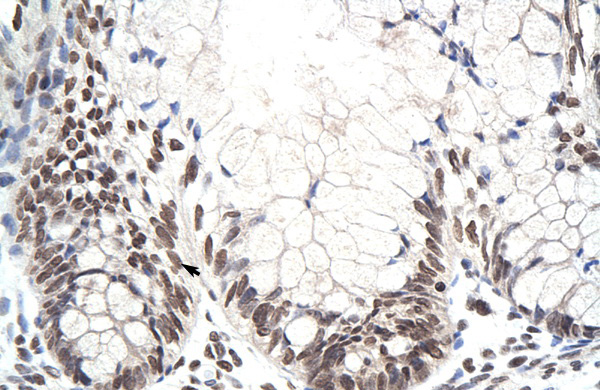

IHC (Immunohistochemistry)

(Rabbit Anti-ZNF394 AntibodyParaffin Embedded Tissue: Human IntestineCellular Data: Epithelial cells of intestinal villasAntibody Concentration: 4.0-8.0 ug/mlMagnification: 400X)